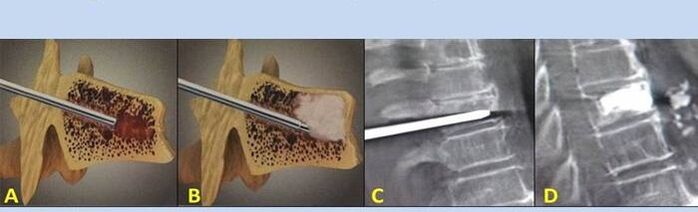

- Nucléoplastie – ablation du noyau du disque intervertébral. L'opération soulage la pression sur les terminaisons nerveuses.

- Vertébroplastie par ponction – méthode de stabilisation des vertèbres. Au cours de l'intervention, le médecin remplit les cavités de la colonne vertébrale avec du ciment osseux.